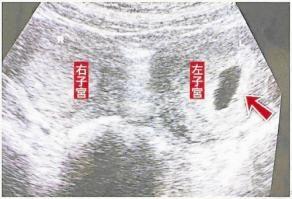

B超结果出来了,检查发现,小文有双阴道,一边大一边小、双宫颈、双子宫。

姜医生解释说:“别担心,小文,这是一种生殖器官畸形,医学上叫做阴道纵膈,一般来说,阴道中隔一般附着在阴道前后壁正中线,纵向走行,可分为部分性及完全性。后者至宫颈部起始,一直伸展至阴道外口,将阴道均分为二,形成双阴道。偶尔也有中隔偏离中线,与阴道侧壁融合,形成阴道斜隔。阴道纵隔一般无症状,有的人直到结婚后因*交性**困难就诊发现。还有的到了分娩阶段,因为难产才明确诊断呢。”